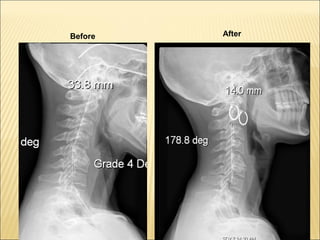

42. 14% reduction in Scoliosis in 90 days in a Patient 68 Y.O. High BP, High Cholesterol, High Blood Sugar Before After